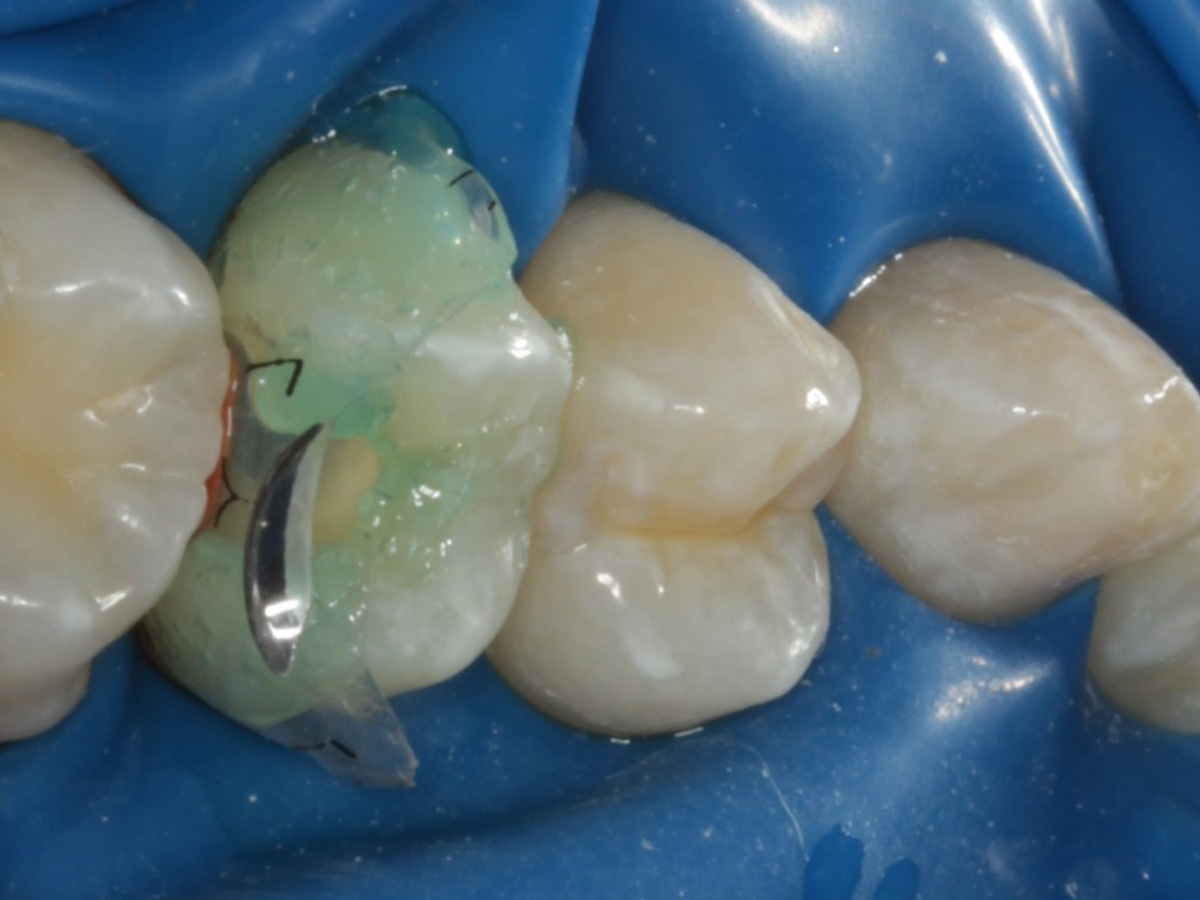

Abbildung 6

Pulpenkavum mit Watte und farbigem Komposit abgedeckt; zuvor Spülung der Wurzelkanäle nur mit NaCl zwecks Nichtgefährdung der Kompositadhäsion